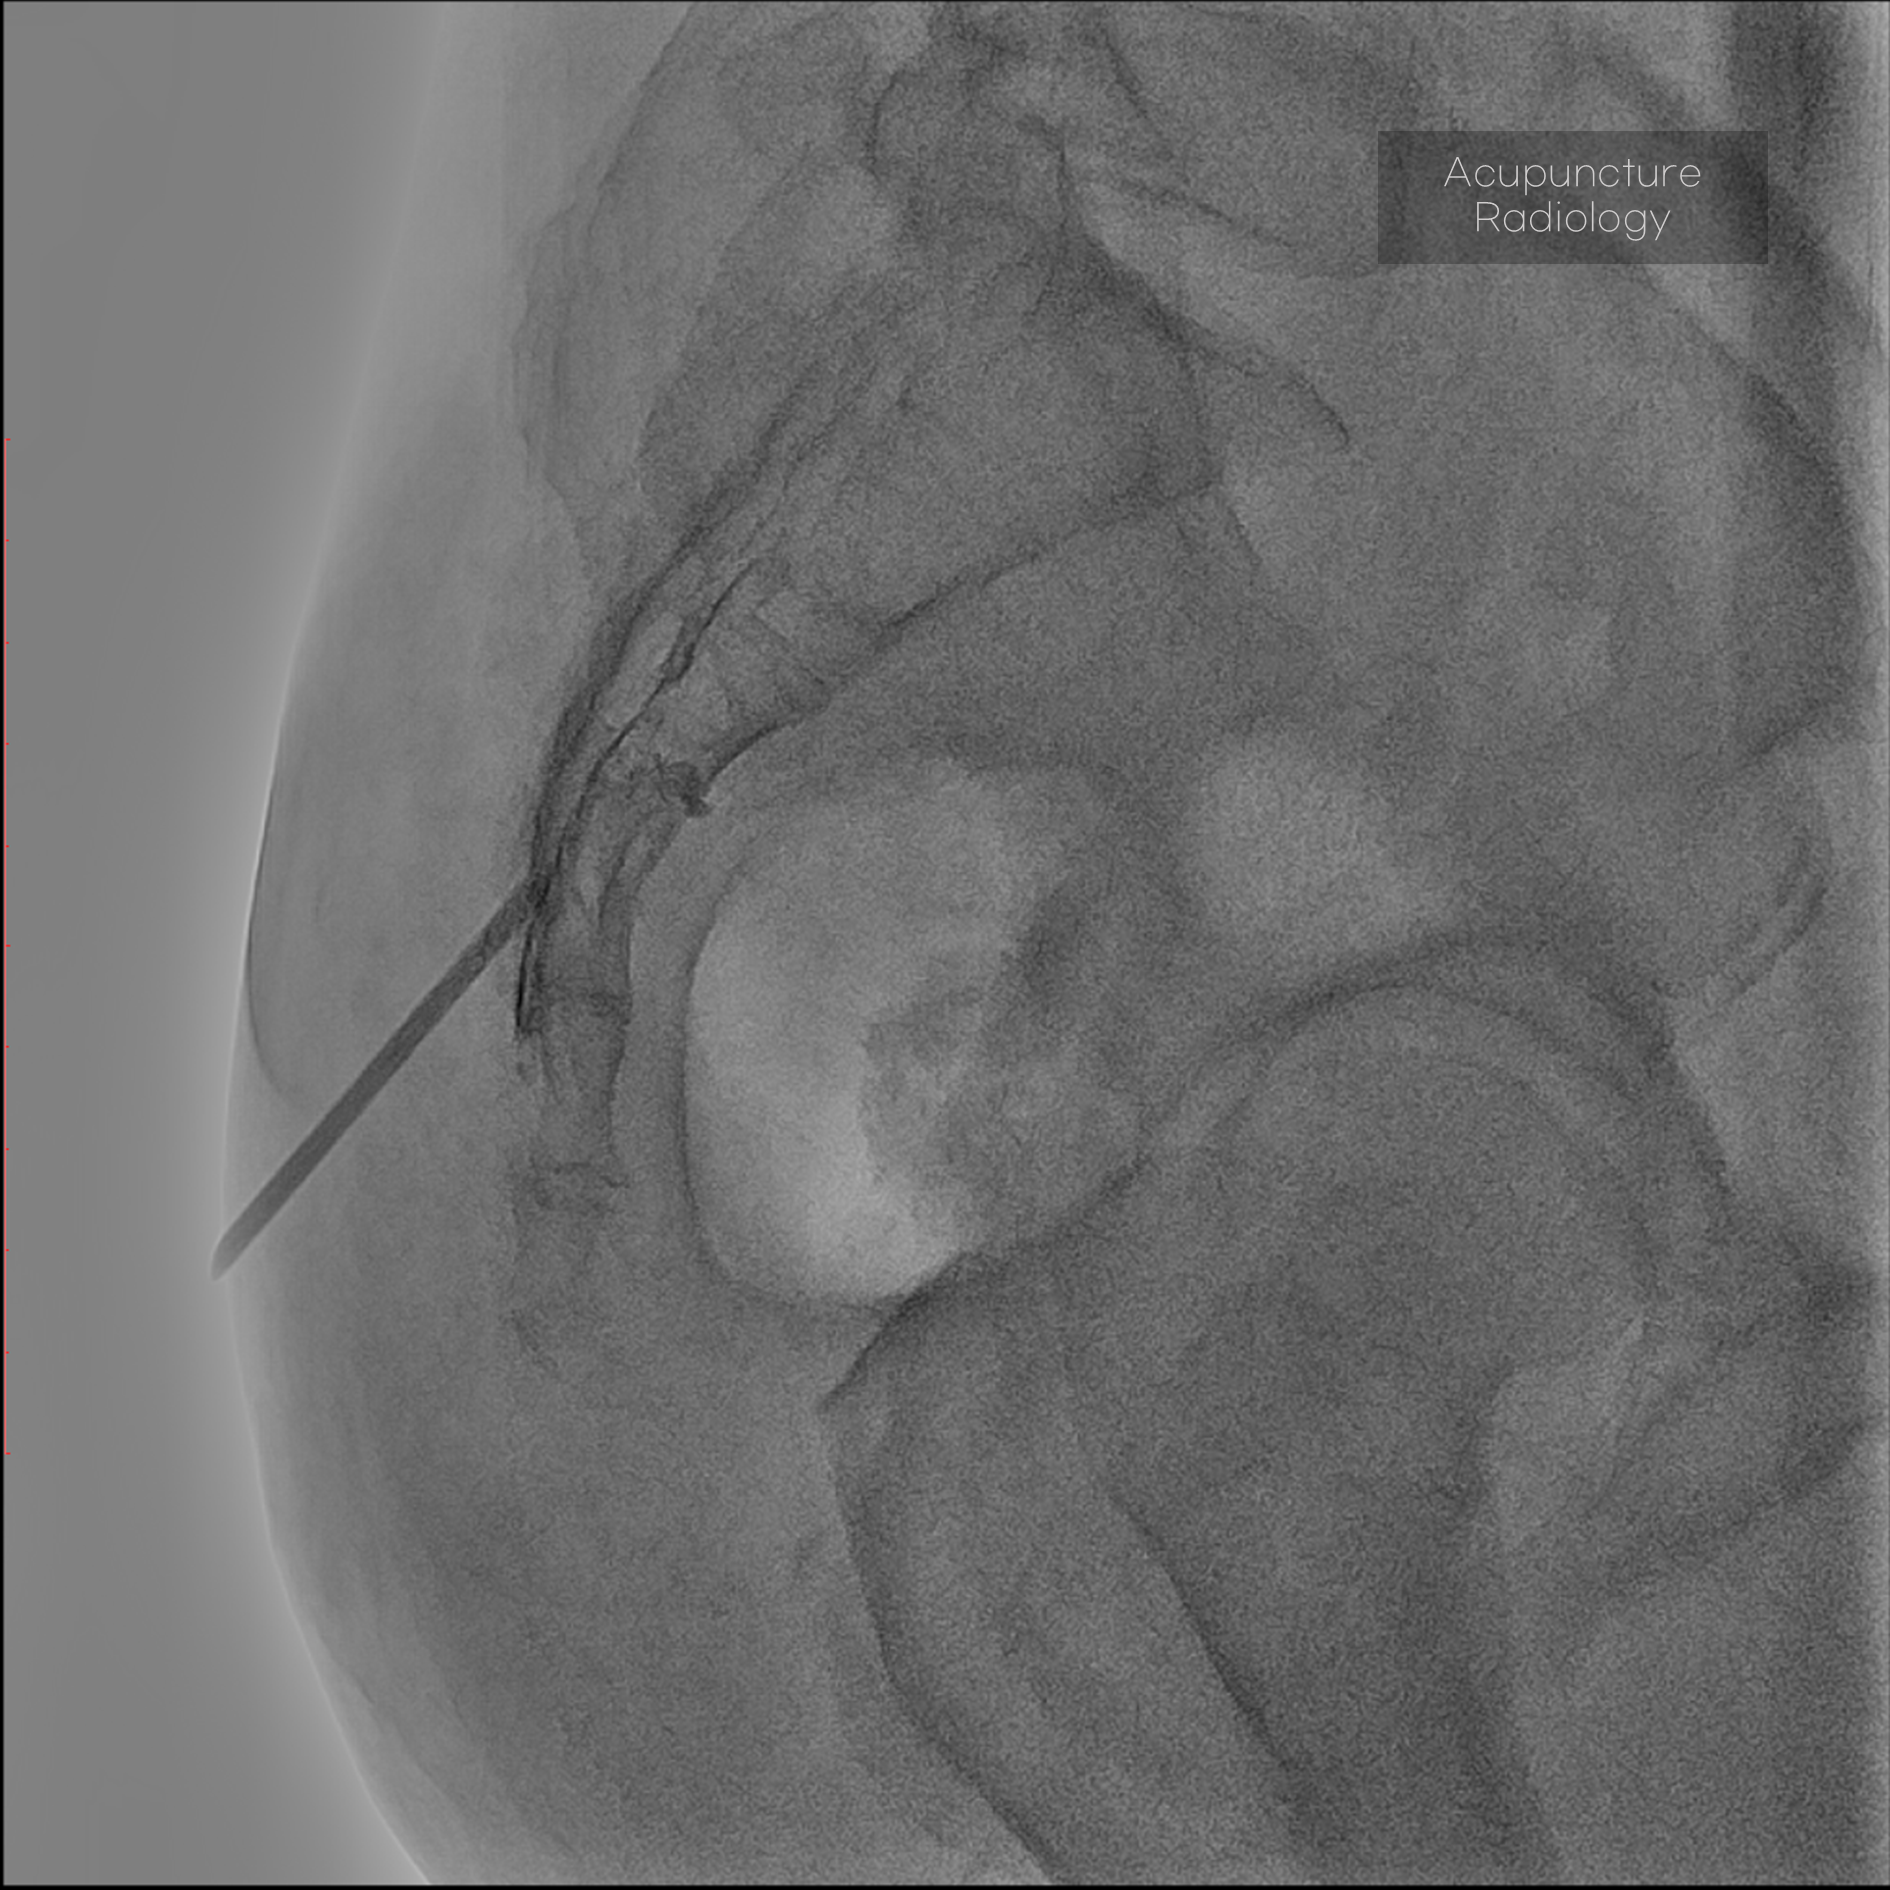

경막외 유착박리술, Epidural Neuroplasty